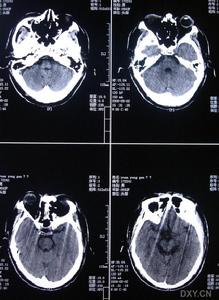

3.MRI是本病的重要診斷工具側腦室周圍及半卵圓中心可見均勻分布的點狀和結節狀T2WI高信號,基底核和腦橋也可見多數病人腦血管造影無異常,曾報告1例患者小動脈嚴重狹窄,另2例患者腦血管造影后神經體徵加重PET檢查僅1例嚴重基底核損傷的躁狂病人提示皮質代謝降低皮膚活檢是腦外部檢查的新手段,皮膚活檢發現嗜鋨顆粒樣物(GOM)沉積有重要診斷價值。可伴明顯抑鬱躁狂和自殺傾向,注意繼發的肺部感染尿路感染及褥瘡等。

影像學上有類似Binswanger病的表現,MRI顯示在腦室周圍白質、腦幹、小腦中腳、基底節區和丘腦部位多發性小的線狀、點狀病灶,可在皮質下對稱融合成片狀。CADASIL臨床確診標準:在可能CADASIL診斷標準的同時,與第19號常染色體連鎖和(或)病理證實有顆粒狀嗜鋨性物質沉積改變的小動脈病。可能為CADASIL的診斷標準:①50歲前發病;②出現下列臨床表現中至少2條:症狀持久的腦卒中發作、偏頭痛、明顯的情感異常、皮質下痴呆;③無腦血管病的危險因素;④常染色體顯性遺傳證據;⑤MRI顯示腦白質異常,而無腦皮質梗死灶。

⑥影像學檢查:MRI顯示非典型性腦白質病。可見,腦室周圍多發的梗死灶及白質變性,可累及兩側半球皮層、白質及腦室周圍、基底節、橋腦白質等部位。

影像學檢查示:患者姐弟的CT均可見,但當地的CT顯示欠清楚。患者的頭顱CT可見多發白質變性;MRI清晰可見多發白質變性及小梗死病灶,病灶大小不一,均呈長T1、長T2信號,病灶累及雙側半球、腦室周圍、腦幹、橋腦,小腦未見病灶;梗死灶分布在底節區,MRA(血管的磁共振影像)顯示顱內血管正常。